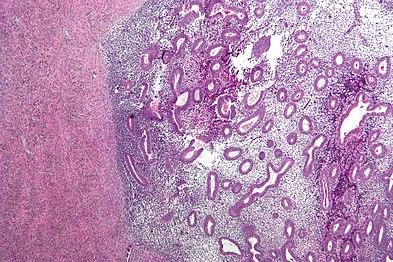

Histopathology

For a histopathological diagnosis, at least two of the following three criteria should be present:[101]